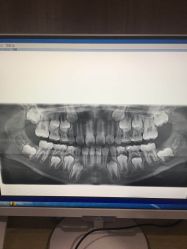

• 医疗健康 齿科 体检中心

口腔齿科 体检中心 医院 药店 中医 宠物医院 整形 妇幼医院 其他医疗

• 睿宝儿科·眼科·口腔(静安大悦城门诊部)

• -睿宝儿科·眼科·口腔(静安大悦城门诊部)